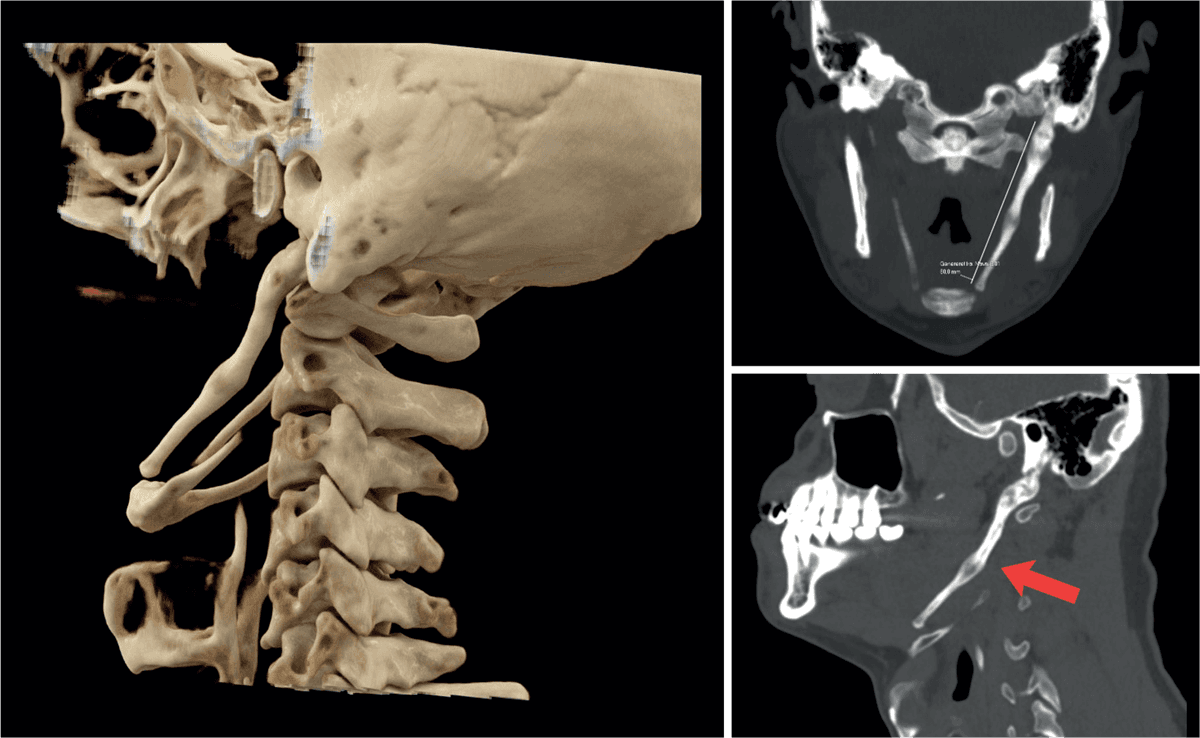

Øre-næse-hals artikler fra Ugeskrift for Læger 20/2025StatusartikelBenigne spytkirteltumorer13. okt. 202512 min.KasuistikIdiopatisk bilateral vestibulopati13. okt. 20255 min.Ugens billedeUspecifikke halssmerter7. jul. 20252 min.KasuistikEksostose ved den indre øregang2. jun. 20254 min.KasuistikKraftig blødning efter biopsi fra nasofaryngealt juvenilt angiofibrom14. jul. 20255 min.StatusartikelNye behandlingsmuligheder for kronisk hoste6. okt. 202513 min.